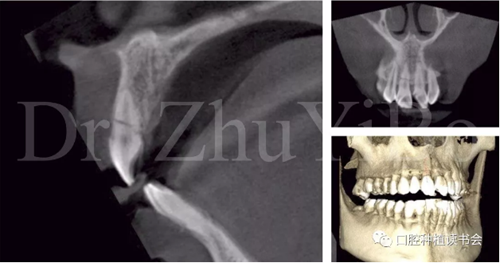

術(shù)前cbct顯示:右上中切牙牙根牙槽突類(lèi)型為一型(圖8)。牙齦為厚型牙齦類(lèi)型;咬合關(guān)系基本正常。

圖8 CBCT:11可見(jiàn)明顯根折線(xiàn),無(wú)法保留